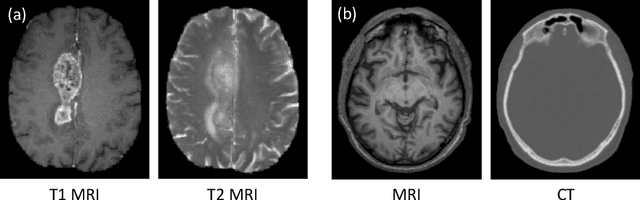

Abstract:Medical imaging plays a critical role in various clinical applications. However, due to multiple considerations such as cost and risk, the acquisition of certain image modalities could be limited. To address this issue, many cross-modality medical image synthesis methods have been proposed. However, the current methods cannot well model the hard-to-synthesis regions (e.g., tumor or lesion regions). To address this issue, we propose a simple but effective strategy, that is, we propose a dual-discriminator (dual-D) adversarial learning system, in which, a global-D is used to make an overall evaluation for the synthetic image, and a local-D is proposed to densely evaluate the local regions of the synthetic image. More importantly, we build an adversarial attention mechanism which targets at better modeling hard-to-synthesize regions (e.g., tumor or lesion regions) based on the local-D. Experimental results show the robustness and accuracy of our method in synthesizing fine-grained target images from the corresponding source images. In particular, we evaluate our method on two datasets, i.e., to address the tasks of generating T2 MRI from T1 MRI for the brain tumor images and generating MRI from CT. Our method outperforms the state-of-the-art methods under comparison in all datasets and tasks. And the proposed difficult-region-aware attention mechanism is also proved to be able to help generate more realistic images, especially for the hard-to-synthesize regions.